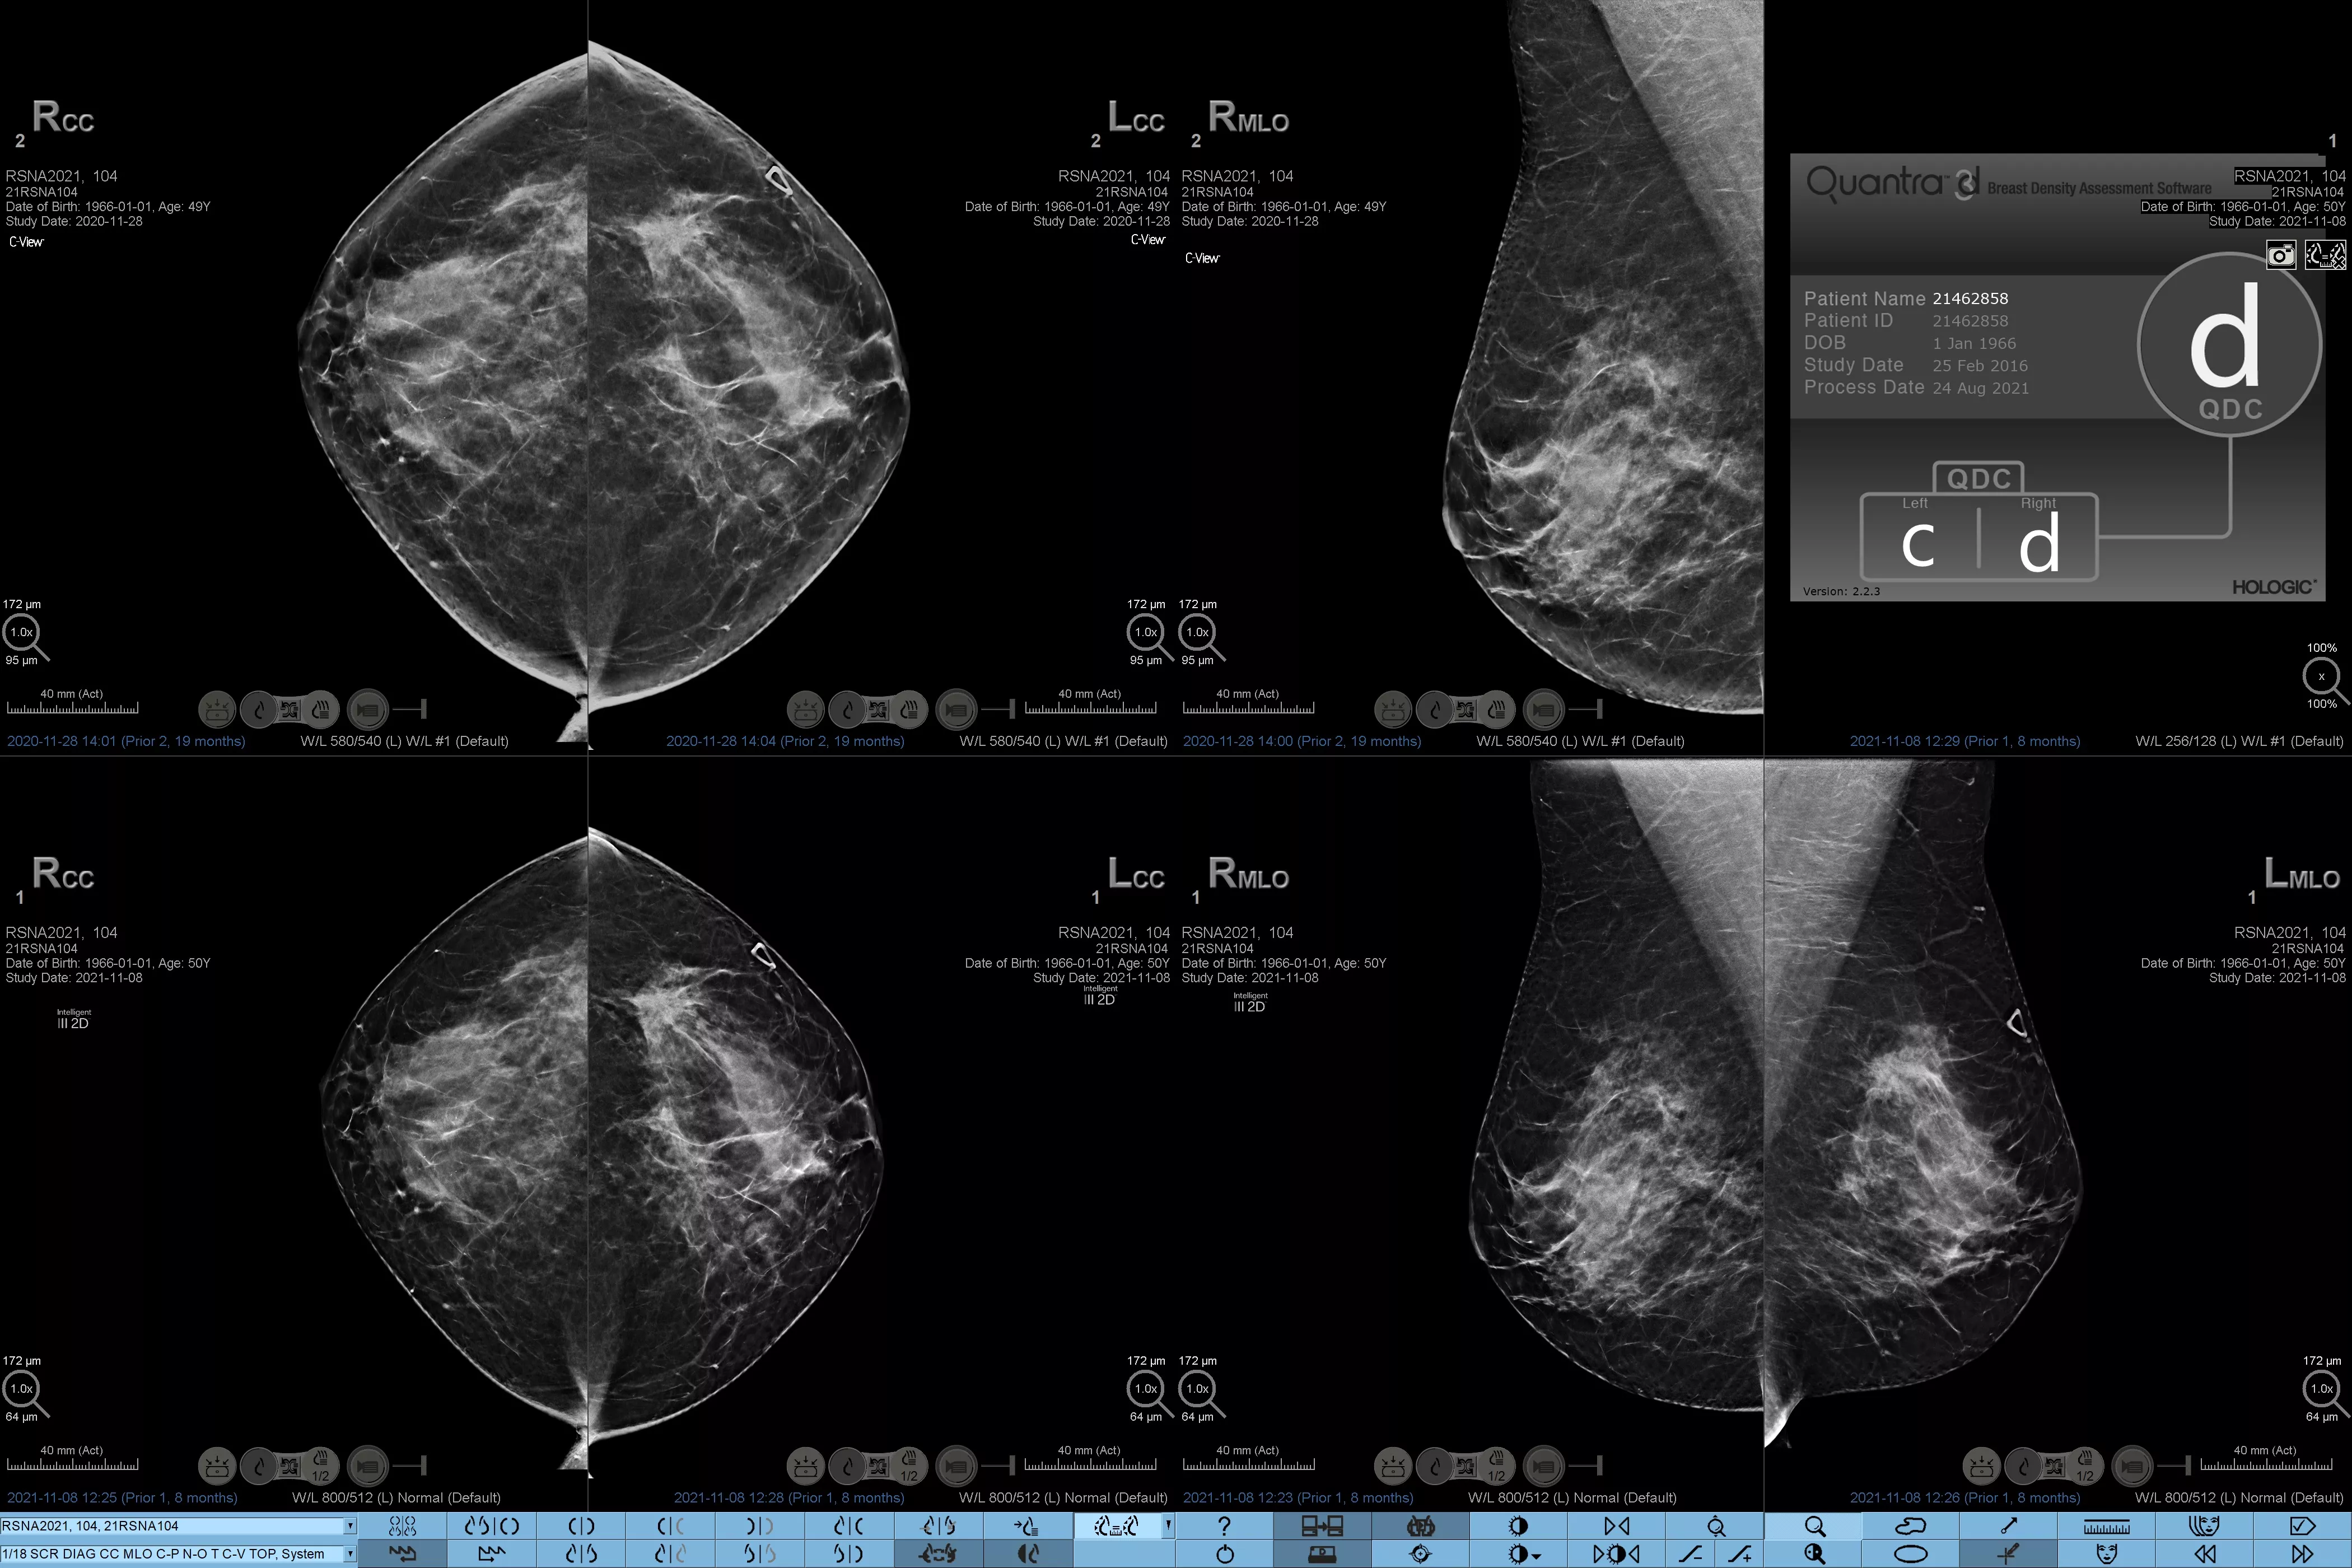

Higher breast density is known to increase a woman’s risk for breast cancer.1 The need for accurate, unbiased analysis is therefore critical. Powered by machine learning, Quantra technology software analyses both 2D™ and tomosynthesis images for distribution and texture of parenchymal tissue. It categorizes breasts in four breast composition categories consistent with guidance from the American College of Radiology (ACR) BI-RADS Atlas 5th Edition.2

8. Breast composition categories as described in ACR BI-RADS Atlas.